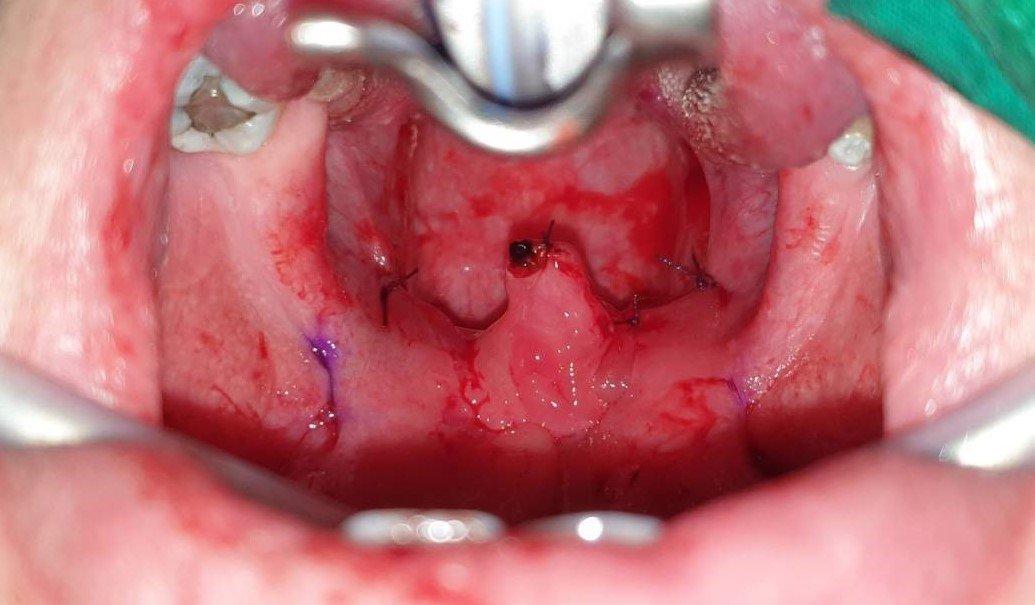

ขั้นตอนการรักษาทำในห้องผ่าตัด (ส่วนมากทำในโรงพยาบาล) โดยใช้ไหมแบบมีเงี่ยง (ชนิดคล้ายกับที่ใช้ยกกระชับใบหน้า) เย็บใต้เยื่อบุบริเวณลิ้นไก่ เพดานอ่อน และคอหอย เพื่อดึงรั้งทำให้ทางเดินหายใจบริเวณคอหอยกว้างขึ้น บางครั้งอาจทำการตัดเนื้อเยื่อที่หย่อนบริเวณลิ้นไก่และเพดานอ่อนออกเล็กน้อยบางส่วน อาจทำร่วมกับการผ่าตัดทอนซิล (tonsillectomy) ตามความเหมาะสม โดยการรักษาจะทำผ่านทางการใส่เครื่องมือทางช่องปาก (ไม่มีแผลที่เห็นได้จากภายนอก) ภายใต้การดมยาสลบ และส่วนใหญ่ใช้เวลาพักรักษาตัวในโรงพยาบาล 1-2 วัน หรืออาจกลับบ้านได้ในวันเดียวกัน